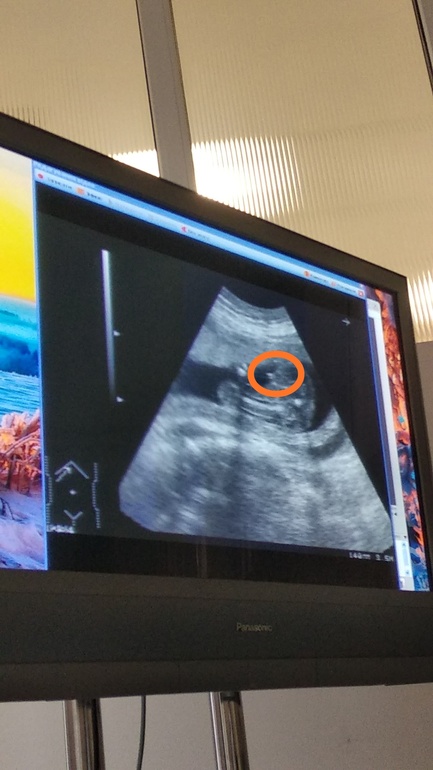

УЗИ 20 недель и пол ребенка

.Сначала предположила один пол,потом второй.Добавлю фото обвела кружочком гениталии ребенка) .Кто хоть не много понимает подскажите.

Девочка скорей всего. Как у нас говорят, три полоски адидас 😅😂 У нас на фото так же было. На второй фотке вообще не поймёшь, что, точно не половые принадлежности, а что-то другое. Для мальчика слишком мало для такого срока.

Что то на 1 снимке непонятно,а на 2 слишком маленькие пречендаллы,,,ну это через чур в 20 недель неувидеть !!у меня тоже до 15 недель девочка была,,а в 17 ,20,23 уже писюн там явный на фото,,и я к нескольким врачам ходила,,и сама на видео снимала,,чтоб уж точно знать кто там у мен,я

Хмммм.....На первом фото девочка похоже, а вот второе это сынишка точно